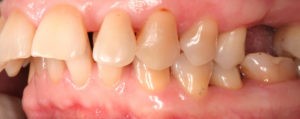

Для предварительной подготовки были привлечены пародонтолог и ортопед, поскольку отсутствие нескольких зубов, заболевание пародонта и дефекты твердых тканей зубов сопутствовали основной патологии. Проведены пародонтологические процедуры, вылечен кариес и его осложнения, изготовлены временные коронки для зубов с большим разрушением. На фото — временные коронки на боковых зубах.

Искривление окклюзионной кривой (плоскости смыкания зубов), возникшее в результате парадонтита, успешно удалось устранить, используя накусочные брекеты на верхних резцах и микроимплант, установленный во фронтальном участке нижней челюсти: